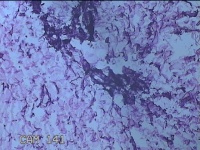

外阴部包块

性别

女

年龄

37岁

临床诊断

皮脂腺囊肿

一般病史

外阴部起包块一月余。

标本名称

大体所见

灰白暗红色包块2.3x1.8x0.8cm一个,表面糜烂,切开包块呈实性,切面灰白淡黄色,质软。

有那么点像脂肪瘤。